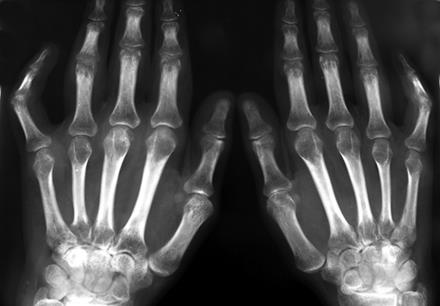

Анализ крови: эритроциты 3, 6 х1012 /л, НЬ 116 г/л, лейкоциты 9х109 /л, СОЭ 50 мм/час. РФ +. На ЭКГ: отсутствие предсердного комплекса, нерегулярно появляющиеся желудочковые комплексы, неодинаковая величина R во всех отведениях. Рентгенография кистей: околосуставной остеопороз, сужение суставных щелей, множественные эрозии.